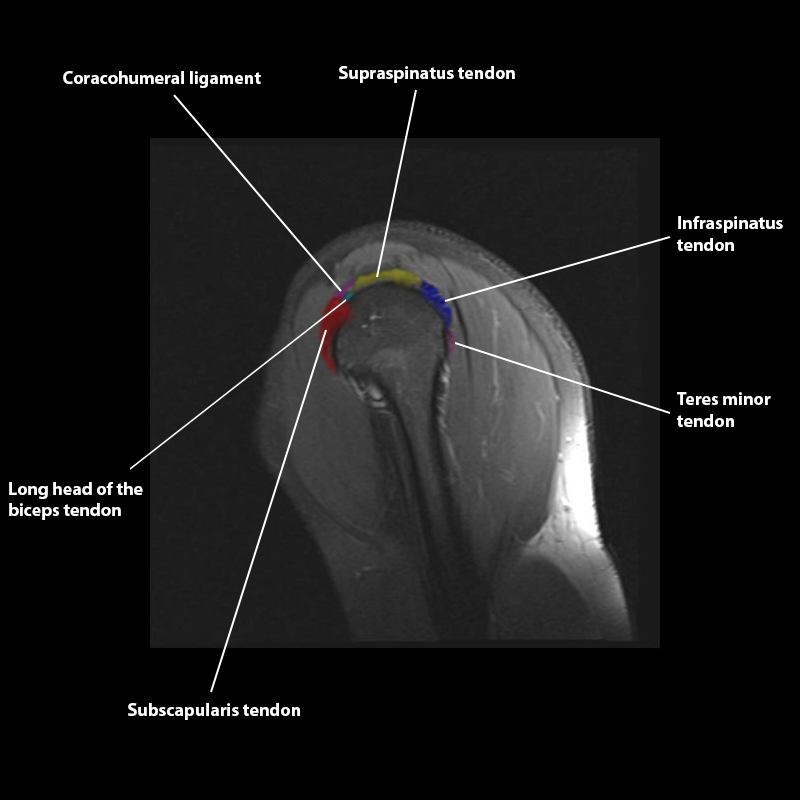

Shoulder MRI Anatomy